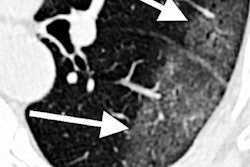

CT scan of lungs of COVID-19 patient with areas described by radiologists as resembling grains of ground glass. Image courtesy of RSNA.The goal of the center is to lead the development and implementation of new diagnostic tools, including machine-learning algorithms, that will enable the rapid and accurate assessment of disease status and help physicians optimize patient treatment.